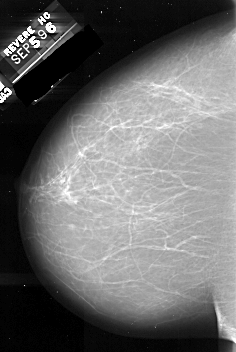

A_1075_1.RIGHT_MLO

RIGHT_MLO LINES 6706 PIXELS_PER_LINE 4231 BITS_PER_PIXEL 16 RESOLUTION 42 OVERLAY